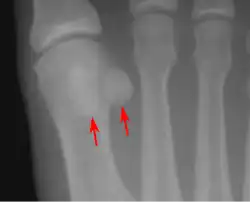

- Zwei Sesambeine liegen unter dem Großzehengrundgelenk in den Sehnen von Musculus abductor hallucis und Musculus adductor hallucis. Zwischen ihnen läuft die Sehne des langen Großzehenbeugers.